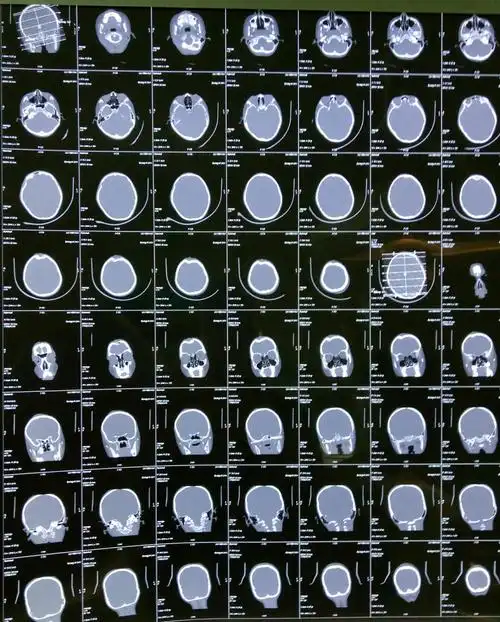

颅骨呈凹陷性粉碎性骨折

矢状窦凹陷性骨折,手术还是保守

额部开放凹陷性骨折

左头顶部开放凹陷粉碎性骨折一例.

额顶部颅骨凹陷性粉碎性骨折一例

开放性粉碎性凹陷性骨折治疗一例